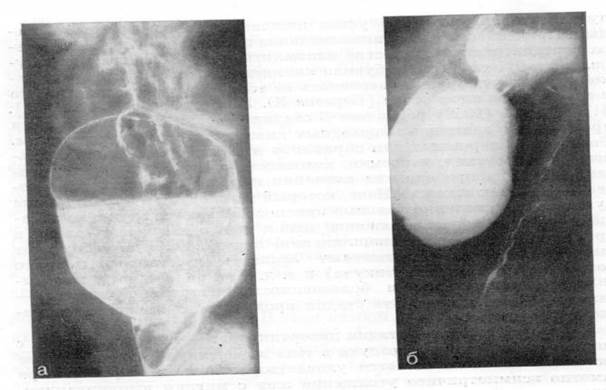

Ведущим методом исследования является многоплоскостное рентгенологическое исследование. Оно позволяет выявить размеры и форму тела дивертикула, длину и ширину, угол перегиба шейки, признаки дивертикулита (рис.2, 3).

Рис.2. Рентгенограмма. Крупный (Ценкеровский) пограничный дивертикул с узкой шейкой и дивертикулит.

Рис.3. Рентгенограмма. Длительный (более 6 ч) застой бария в дивертикуле Ценкера.